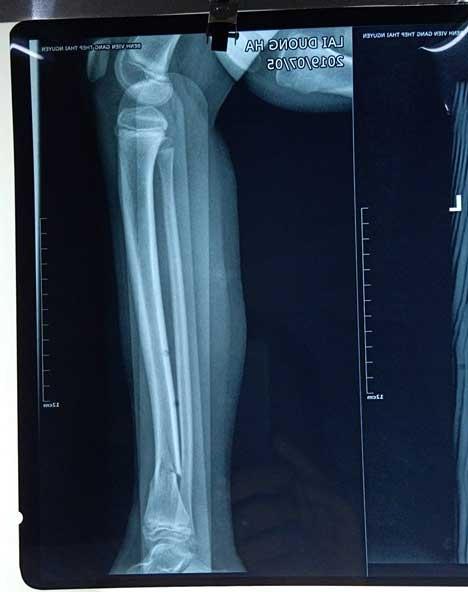

Sau đó, chiếc xe ô tô tiếp tục đi một đoạn rồi lao sang làn đường ngược chiều, đâm vào 2 mẹ con đi xe máy, khiến 2 người bay lên vỉa hè. Cú đâm quá mạnh khiến con gái bị gãy xương cẳng chân, người mẹ bị gãy xương sườn. .

Con gái nạn nhân bị gãy chân